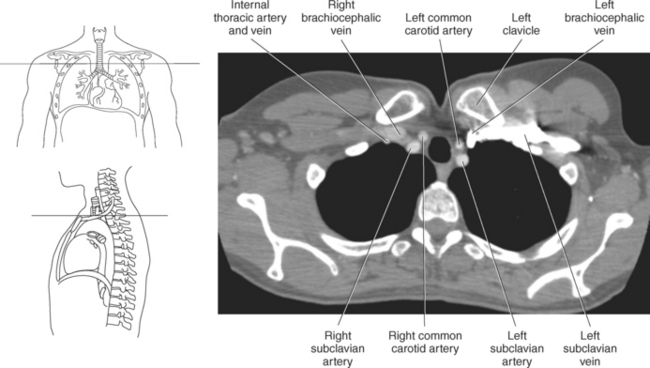

The three main branches of the aortic arch are the brachiocephalic trunk, left common carotid artery, and left subclavian artery (Figure 6.84). The brachiocephalic (innominate) trunk is the first major vessel and the largest branch arising from the aortic arch. It ascends obliquely to the upper border of the right sternoclavicular joint, where it divides into the right common carotid and right subclavian arteries (Figures 6.85 and 6.86). The right common carotid artery ascends the neck lateral to the trachea to the level of C4, where it divides into the right external and internal carotid arteries. The right subclavian artery curves posterior to the clavicle into the axillary region, where it becomes the right axillary artery. The left common carotid artery is the second vessel to branch from the aortic arch. It arises just behind the left sternoclavicular joint and ascends into the neck along the left side of the trachea to the level of C4, where it bifurcates into the left external and internal carotid arteries. The left subclavian artery arises from the aortic arch posterior to the left common carotid artery and arches laterally toward the axilla in a manner similar to that of the right subclavian artery, where it continues as the left axillary artery (Figures 6.85 through 6.88). The right and left internal thoracic arteries arise from the respective subclavian artery at the base of the neck. They run deep to the ribs, just lateral to the sternum, to supply blood to the anterior portion of the thorax (Figure 6.89). The common carotid arteries supply blood to the head and neck, whereas the subclavian arteries supply blood to the upper extremities.

The superior vena cava receives blood from the head and neck via the internal and external jugular veins and from the upper extremities via the subclavian veins (Figures 6.84 and 6.90). The subclavian veins arise from the axillary veins and course posterior to the clavicles. They receive blood from the external jugular veins before uniting with the internal jugular veins behind the sternoclavicular joints, where they continue as the brachiocephalic veins. The left brachiocephalic vein courses across the midline, anterior to the branches of the aorta, to unite with the right brachiocephalic vein just posterior to the costal cartilage of the right first rib. The union of the two brachiocephalic veins forms the superior vena cava, which empties into the right atrium of the heart (Figures 6.75 and 6.76).